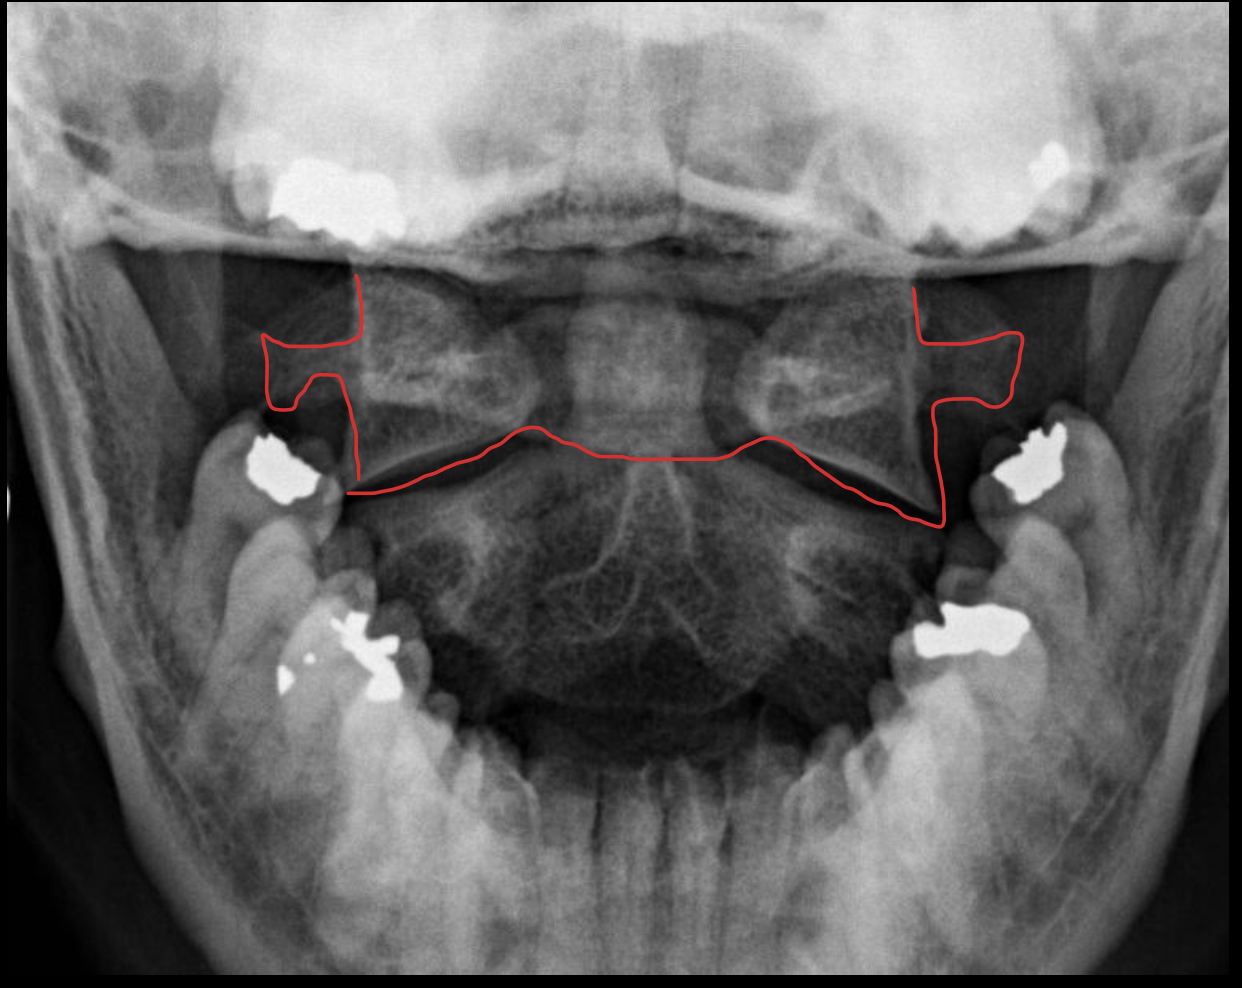

Odontoid process C1

C1 lateral mass

C1